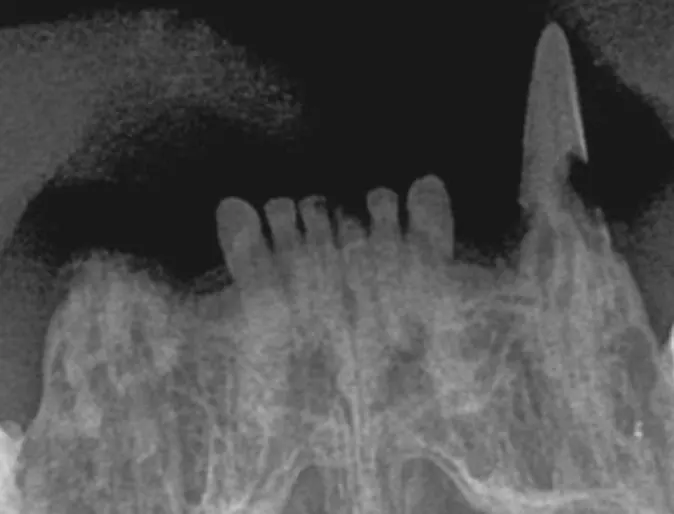

Normal cat upper incisors and canine teeth

Resorptive lesions affecting roots and crowns